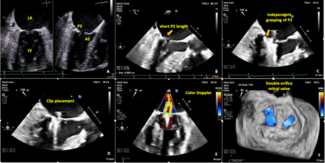

A 75-year-old woman with a history of heart failure was referred for dyspnea upon exertion due to severe mitral regurgitation.